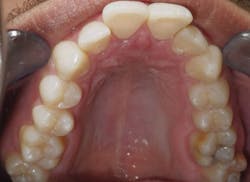

Case 2: 48-year-old female: 15-month clear aligner treatment. This case demonstrates an improvement in a remodeled alveolar complex and an increase in vertical dimension. Case and photos courtesy of Dr. Ben Miraglia.

Before: V-shaped arch. After: U-shaped arch.